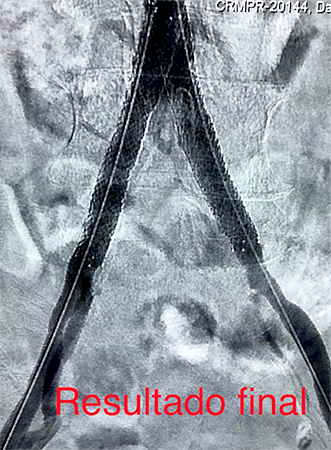

Tratamento de Aneurismas de Aorta, Periféricos ou Vicerais

É o tratamento de artérias dilatadas por métodos endovasculares pouco invasivos. O procedimento pode alterar de acordo com a região localizada, do tamanho e da condição do aneurisma. Atualmente a cirurgia vascular dispõe em seu arsenal para o tratamento de aneurismas, um método seguro e menos invasivo que a cirurgia convencional. O tratamento endovascular para aneurismas de aorta, viscerais e periféricos possibilita uma melhora na qualidade de vida dos pacientes de uma forma menos agressiva, objetivando evitar as principais complicações dessas doenças. São utilizados dispositivos de implante totalmente percutâneo e o procedimento é realizado em local específico para estes casos. Após detalhada análise de exames complementares: ultrassom, angiotomografia, angiorressonância, o cirurgião vascular opta pela melhor alternativa de tratamento baseado na anatomia da doença e no perfil de cada paciente.